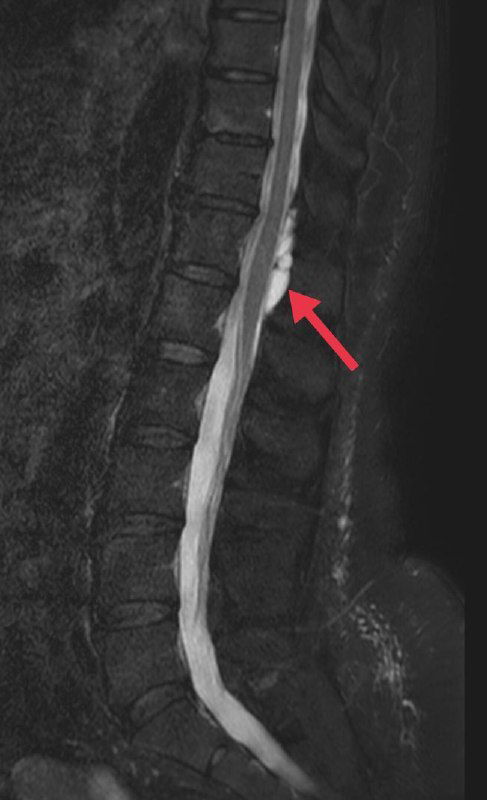

На снимках - эпидуральная киста, сформировавшаяся после повторных эпидуральных анестезий, которая вызывала стойкие нейропатические боли.